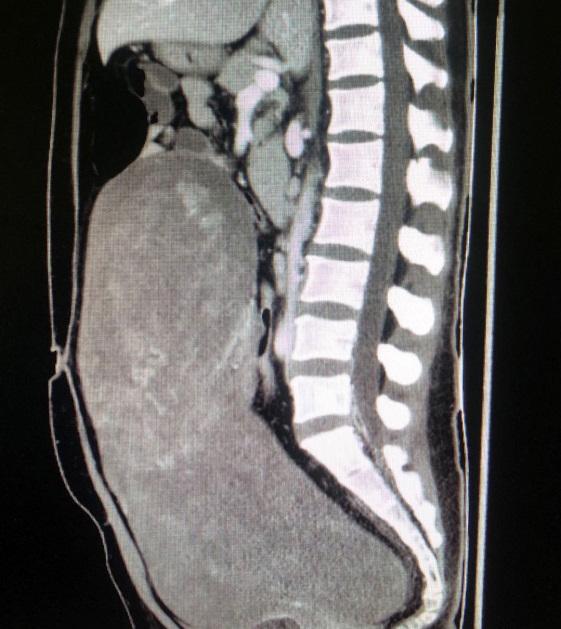

去年11月开始,42岁的张女士突感腹部胀痛难忍,肚子日渐肿胀,腹围增大。2周后,于当地医院就诊,经检查显示,张女士的腹腔内有一巨大肿物,医生建议张女士尽快转诊上级医院进行手术治疗,否则将有生命危险。了解到北京友谊医院肿瘤救治的综合实力后,张女士在家人的陪同下慕名前来就诊。经诊断,张女士盆腹腔瘤体巨大,上界达膈下,向下充满盆腹腔,侵袭范围如此之大的盆腔肿物非常罕见。为了能准确评估肿瘤来源,血供、侵及范围,以便后续手术治疗,需要对张女士进行增强影像学检查。但因患者本身患有输尿管、肾结石,加上肿瘤压迫,导致肾功能不全,处于肾衰竭边缘,如若进行增强影像学检查会有急性肾衰竭的危险。

针对张女士的情况,妇产科组织全院专家会诊。多科室专家讨论后认为,她的盆腹腔巨大肿瘤不除外子宫血管平滑肌瘤或卵巢巨大肿瘤可能,若没有增强影像学检查评估,后续手术风险极大。因此,决定先行双侧输尿管支架置入术,缓解其尿路梗阻;监测她的肾功能情况,待有所好转后,再行增强CT检查及三维血管重建,并进行肿瘤切除手术治疗。

12月10日,泌尿科医师宁晨为张女士成功放置双侧输尿管支架,引流出脓性尿液。经抗感染治疗,张女士血肌酐轻微降落。在影像科大力协助下进行了增强CT检查及三维血管重建。

12月18日上午,经过了充分的术前准备,手术正式开始。麻醉科主任医师柯敬东担任主麻医师,手术由妇产科郝增平主任主持,主任医师金影、主治医师金华共同操刀手术。手术团队在开腹探查后发现患者盆腹腔巨大肿瘤长径40cm,来自左侧子宫阔韧带,压迫周围组织呈膨胀性生长,达上腹腔,瘤体表面血运丰富,并与肠管及周围组织粘连。郝增平主任有着妇科大型疑难手术丰富的经验,在金影主任医师的默契配合下,一步一步小心的分离粘连并牢靠止血,经细致谨慎的操作,该手术历时2个小时终于顺利完成,术中出血仅100ml。该瘤体体积40cm×31cm×20cm,重达13斤,术后诊断为子宫阔韧带粘液样及脂肪平滑肌瘤。张女士术后恢复良好,7天后康复出院。手术后肾功能逐渐恢复正常,于当地医院定期随访。